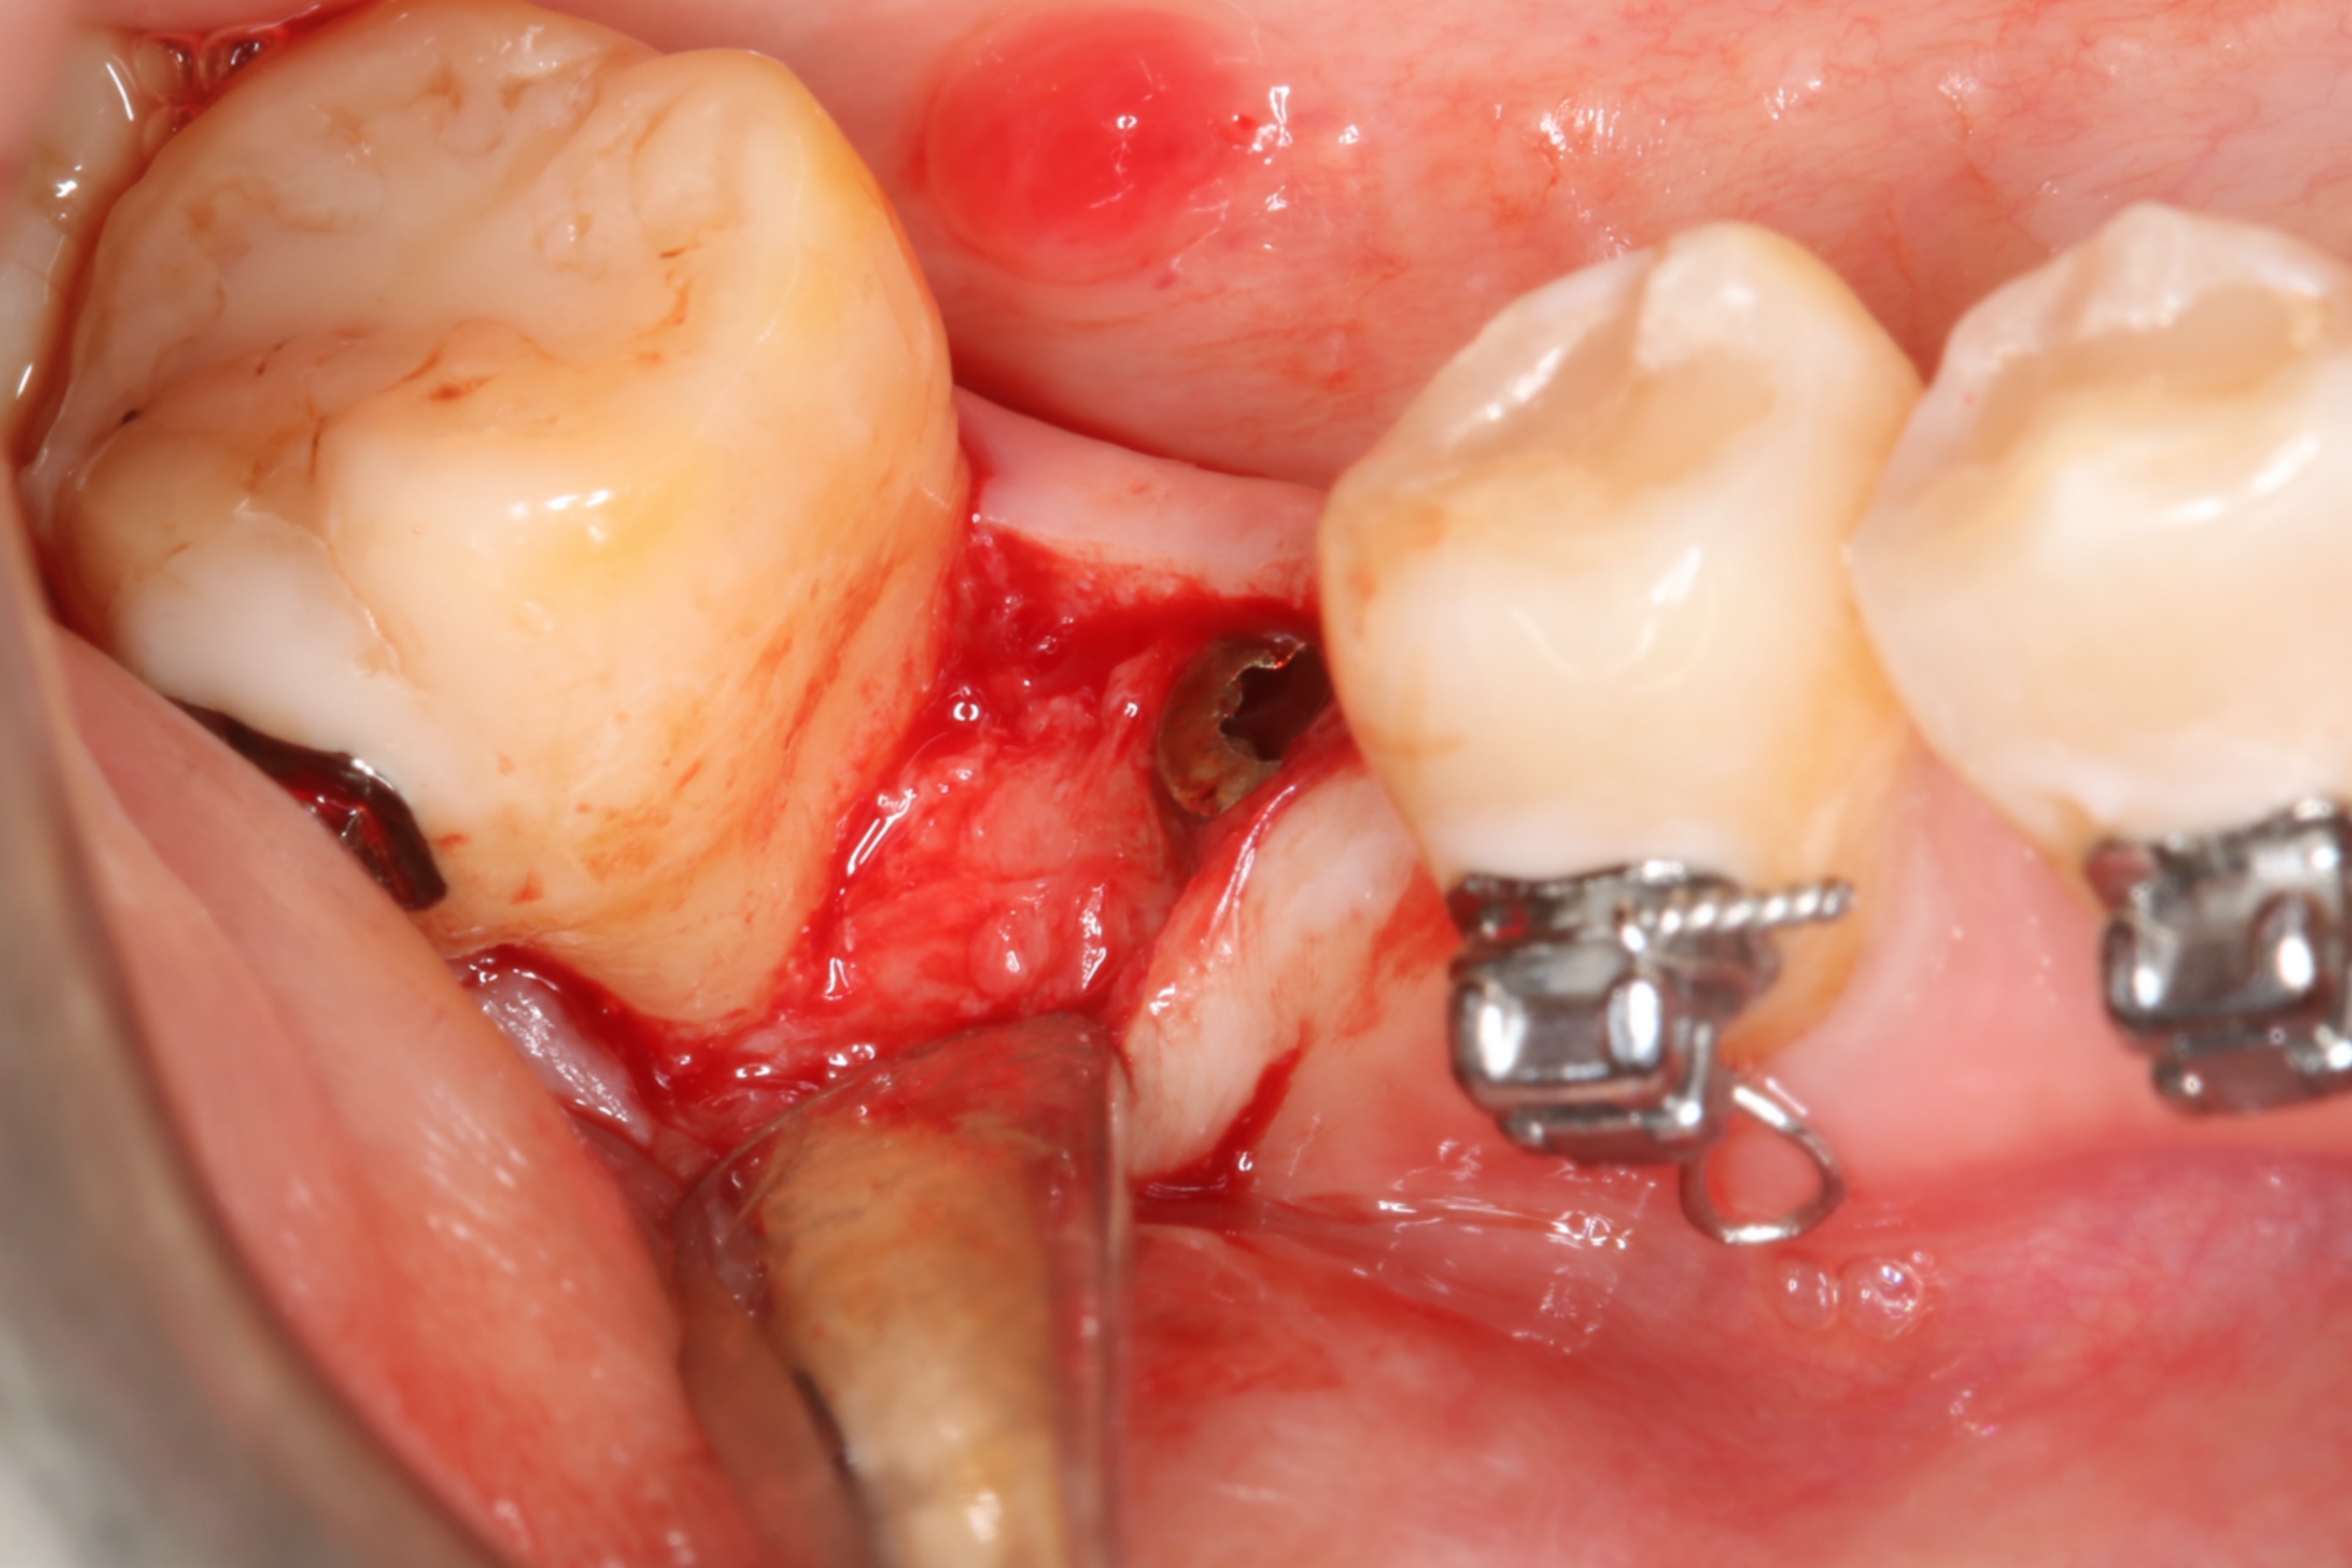

●第七章,澳洲學者Stephen Chen撰寫的立即植牙,同時也有詳細的立即假牙的照片。挑選案例也是用最嚴謹保守條件:厚的牙肉、幾無缺損的骨板、無感染狀態來製作。對我來說,雖然自己不常製作植體假牙,但也對假牙製作的照片,其精緻詳細程度,讚嘆不已。